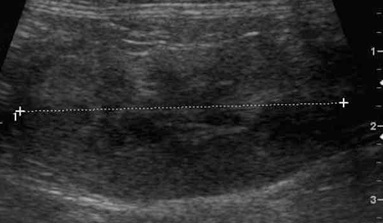

고양이의 신장은 매우 공 같으며, 개보다 유동성이 심합니다. 따라서 프로브를 통해 압박을 가할 때 신장이 빠져나가지 않게 조심스럽게 접근해야 합니다. 중간 주파수의 convex 프로브(7.5-9MHz)로 적절한 영상을 획득할 수 있으며, 더욱 자세한 영상을 얻기 위해서는 보다 높은 주파수의 linear 프로브(10-14MHz)를 이용할 수 있습니다. 그리고 신장은 서로 직각 방향의 방향에서 관찰하는 것이 중요합니다(그림 1 & 2).

정상 신장의 모양은 난원형 혹은 콩 모양을 보이며, 피질(cortex), 수질(medulla) 및 신동(sinus)으로 구분됩니다. 신장의 trans view에선 신우도 관찰할 수 있습니다. 피질은 균일한 에코를 가지며, 간과 비교 시 약간의 저에코 혹은 같은 동에코, 비장과 비교 시에는 저에코성을 보입니다. 정상 고양이에서 근위세뇨관 상피의 지방축적이 많으면 피질의 에코가 증가하여 간보다 에코성이 높아 보일 수 있고, 특히 노령묘, 거세한 수컷과 임신한 고양이에서 이런 현상을 보입니다. 수질은 저에코성~무에코성을 나타내며, 신동은 신문의 중심부로서 지방의 존재로 고에코성을 보입니다.

신우는 보통 보이지 않으나, trans view를 잘 잡으면 보일 수 있습니다(그림 2). 신우의 폭은 1-2mm로 무에코의 선으로 관찰됩니다. 수액 투여 시에는 일시적 확장이 있으며, 결석으로 인한 요도폐색, 종양, 이소성 요관이나 신우신염이 있을 때는 확장이 될 수 있습니다(Table 2, 그림 3). 또한 leptospirosis, 신장의 말기 상태나 신장이식 등에서도 나타날 수 있습니다3).